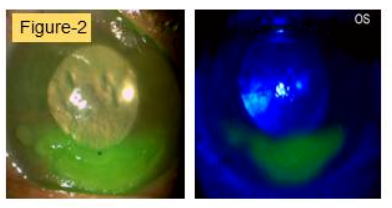

图2.次日,中央出现上皮水疱,下方新月形缺损伴基质浸润(计划开始抗病毒治疗)